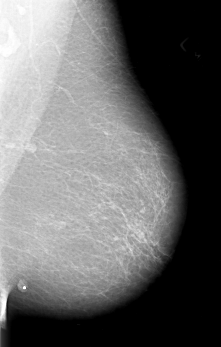

B_3010_1.RIGHT_MLO

B_3010_1.LEFT_MLO

B_3010_1.RIGHT_CC

B_3010_1.LEFT_CC

DATE_OF_STUDY 5 6 1995

PATIENT_AGE 65

DENSITY 1

LESION_TYPE MASS SHAPE IRREGULAR MARGINS ILL_DEFINED

ASSESSMENT 4

SUBTLETY 3

PATHOLOGY MALIGNANT